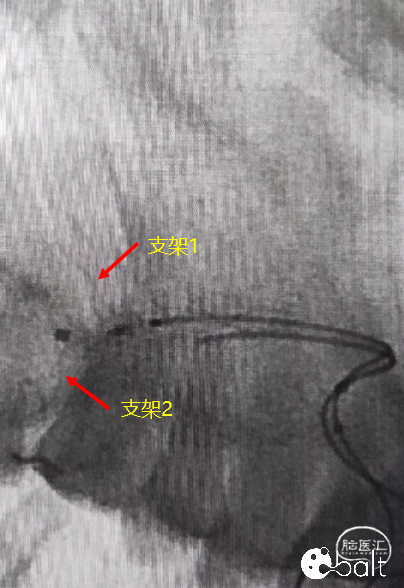

支架放置如图所示:

上干支血管成角较锐,且相对下干支更粗,更直,适合放置相对较长的支架,以方便覆盖更多瘤颈。下干支偏细,且迂曲的远端不利于支架释放,适合短支架,便于打开和保护瘤颈。

3、第一条支架全放,微导管穿支架网孔半释放另一条支架后填圈。

支架微导管优先超选成角相对较锐的上干支血管进行支架释放,以便于后续穿网孔释放另一条支架。

02

全释放上干支支架,覆盖部分瘤颈。

03

微导管穿支架网孔,上干支释放的支架,在转弯处LEO支架滑动单元格设计的特点使外侧弯网孔相对更大,有利于穿网孔操作。

04

第二枚支架半释放至覆盖剩余部分瘤颈,为填圈做准备。